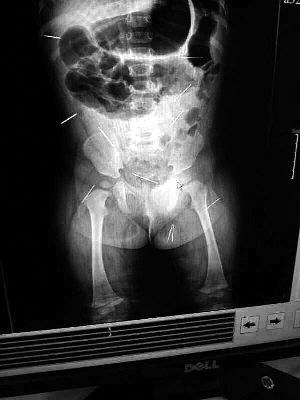

山東聊城11個月女嬰萱萱(化名)疑似被人以12根鋼針插滿臀部、腹腔等部位,昨天在兒童醫(yī)院會診后,醫(yī)生稱3根針靠近胸腔最危險,首批先行取出,預計將在下周二手術。孩子父母稱孩子一直由家人照顧,自家與他人并無冤怨。山東警方表示正在偵破中,不便透露案情。

“要不是當初那幾個紅點,可能到現(xiàn)在我們還不知道孩子身體里有鋼針!”昨天,在兒童醫(yī)院住院處,萱萱爸爸范先生稱,日前原本很愛笑的萱萱突然變得有些焦躁,一抱起來就哭,孩子母親偶然間在萱萱屁股上發(fā)現(xiàn)了幾個小紅點兒,原以為是蚊蟲叮咬,就醫(yī)結果卻讓人不寒而栗?!搬t(yī)院拍出的片子上,萱萱的體內(nèi)有12根鋼針,插滿臀部、腹腔、骨盆等各個部位。”范先生介紹,因為鋼針已深入體內(nèi),要是孩子不哭鬧,他們很難發(fā)現(xiàn)。

北京晨報記者了解到,目前體內(nèi)的12根鋼針多分布在孩子的臀部,一根在腹部,其余3根在胸腔附近,其中一根很接近心臟?!耙驗楹⒆犹。t(yī)生們害怕取針的時候?qū)λ斐蓚?,在胸腔附近?針可能會威脅她的生命”。

截至昨晚6時許,北京晨報記者從兒童醫(yī)院宣傳部門了解到,孩子目前已經(jīng)接受完專家會診,暫定今天和下周一進行術前檢查,如果一切順利將在下周二手術,“孩子暫時沒有生命危險”。